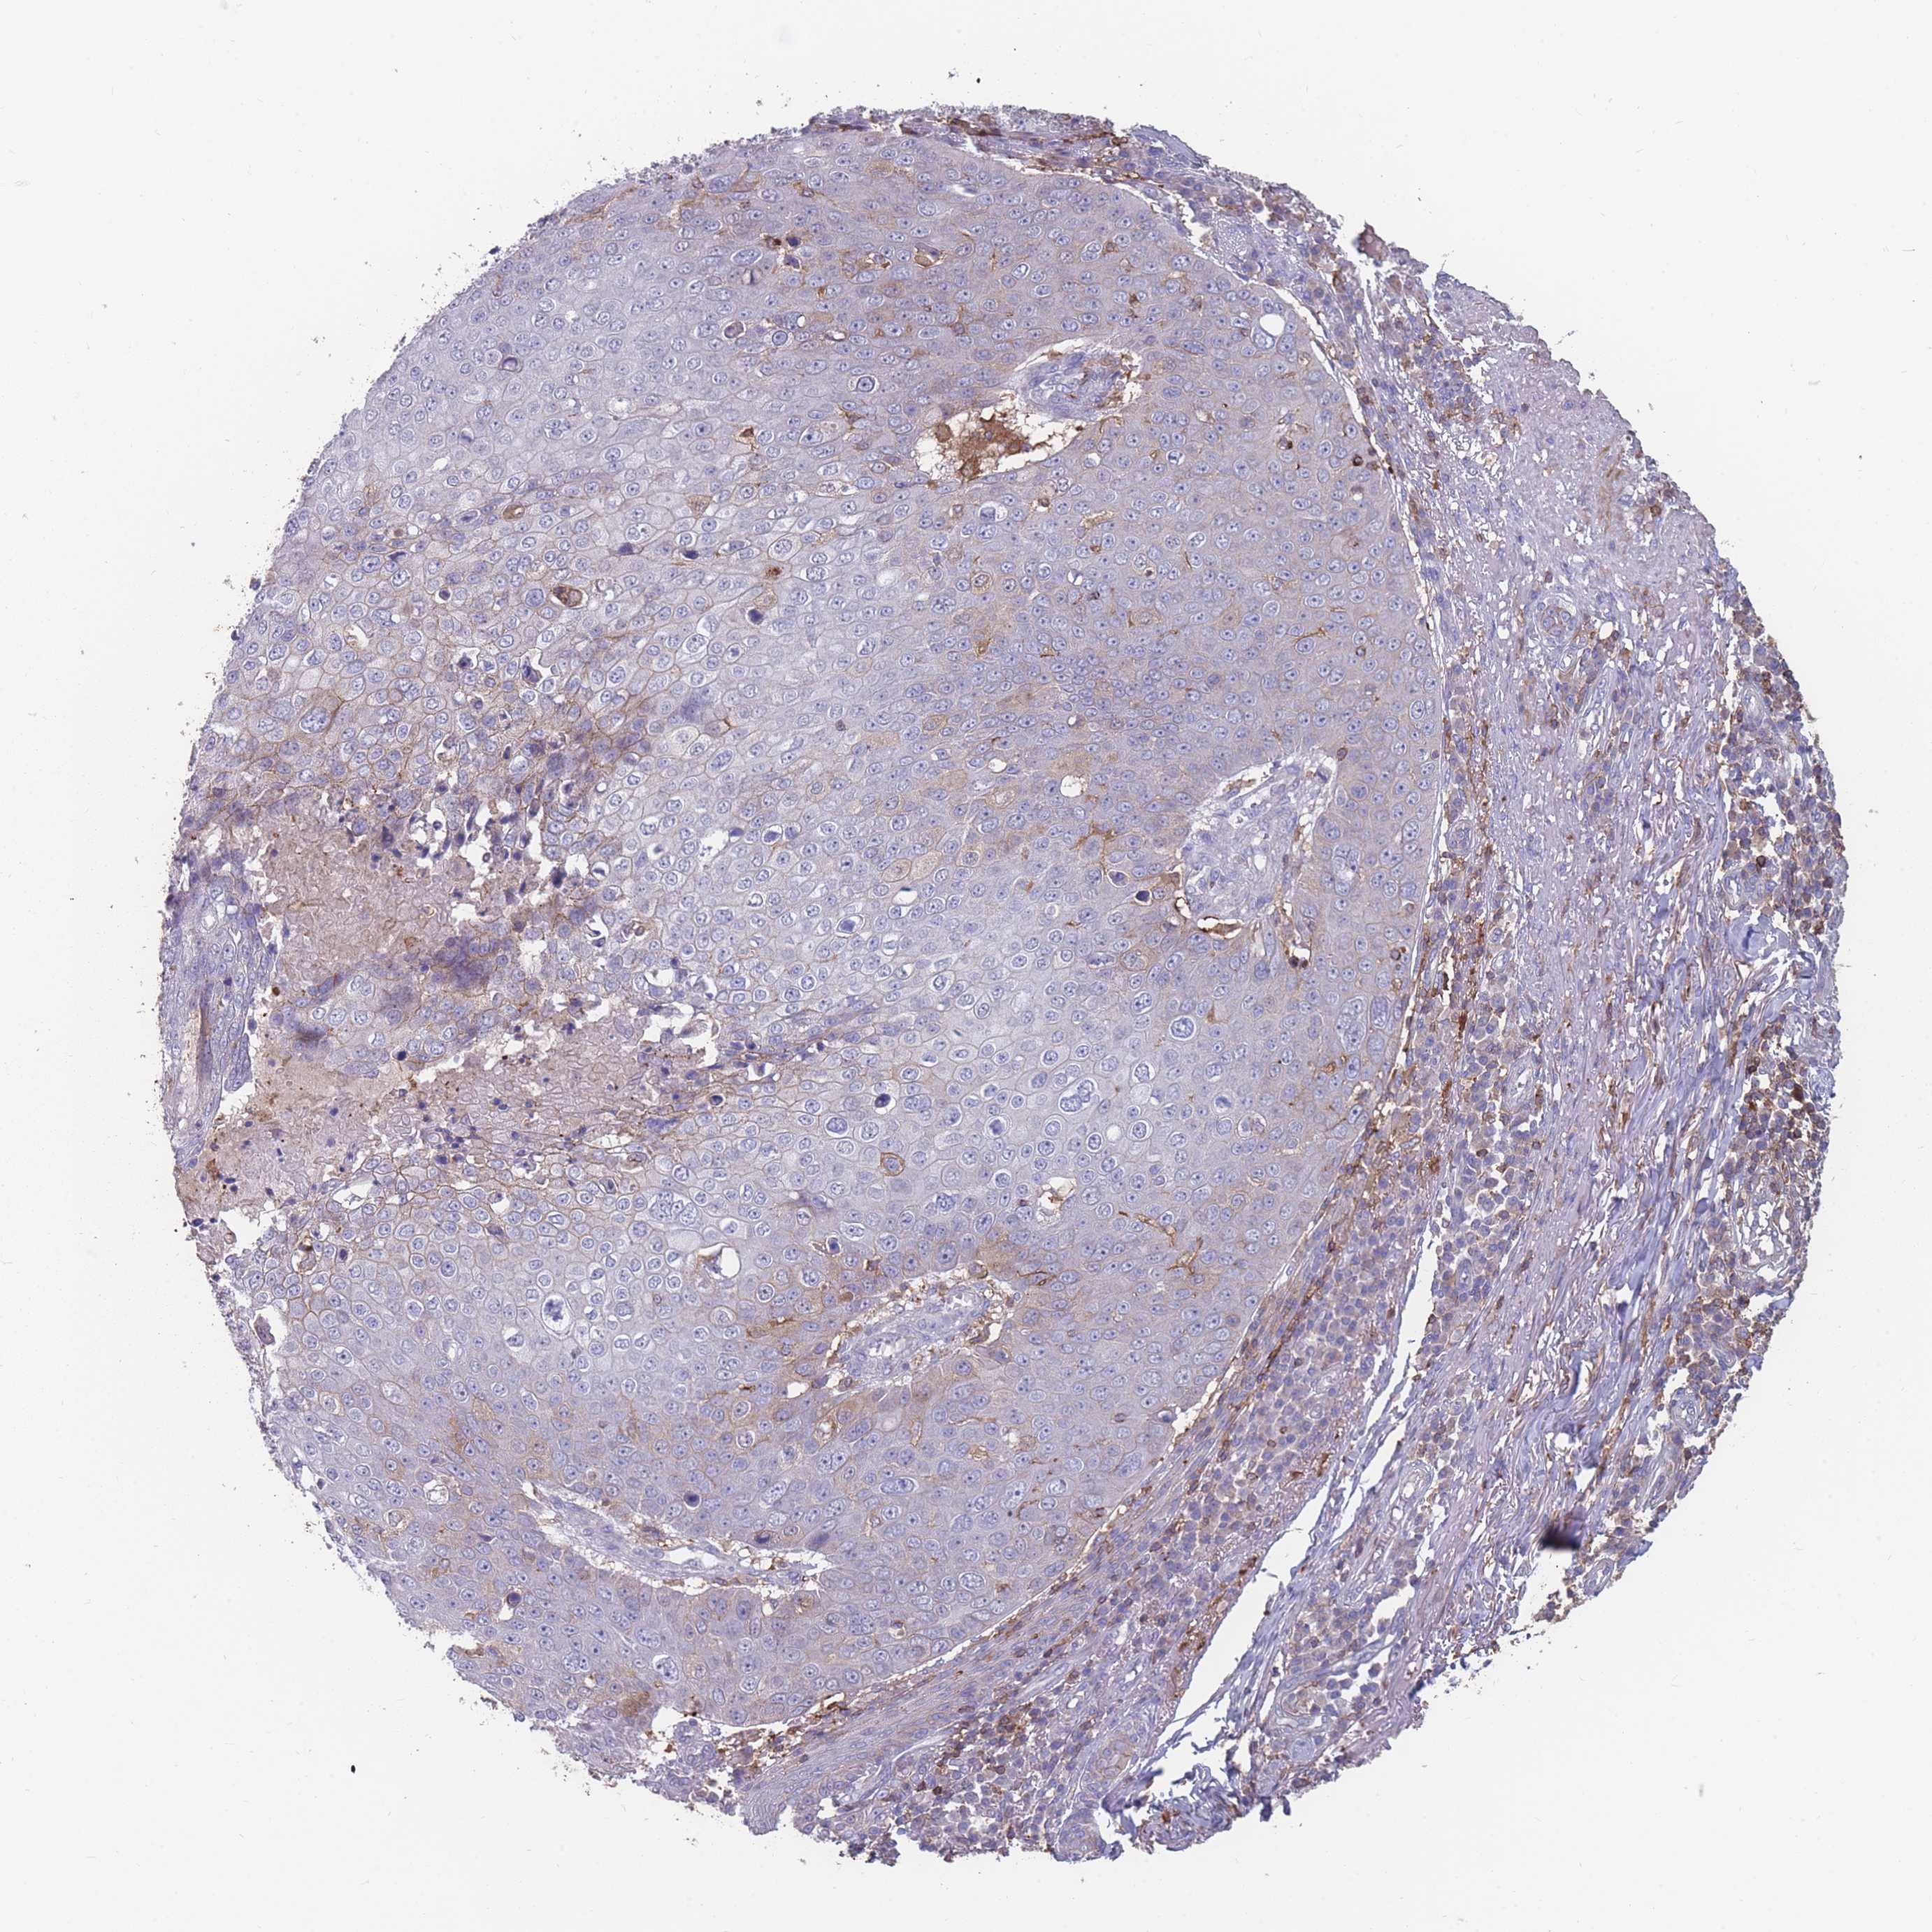

SKIN CANCER - Protein expressioni

A mouse-over function shows sample information and annotation data. Click on an image to view it in a full screen mode. Samples can be filtered based on level of antibody staining by selecting one or several of the following categories: high, medium, low and not detected. The assay and annotation is described here.

Each image is clickable and will lead to virtual microscopy that enables deeper exploration of all samples and also displays staining intensity scores, fraction scores and subcellular localization as well as patient and tissue information for each sample.

Antibody HPA035832

Basal cell carcinoma